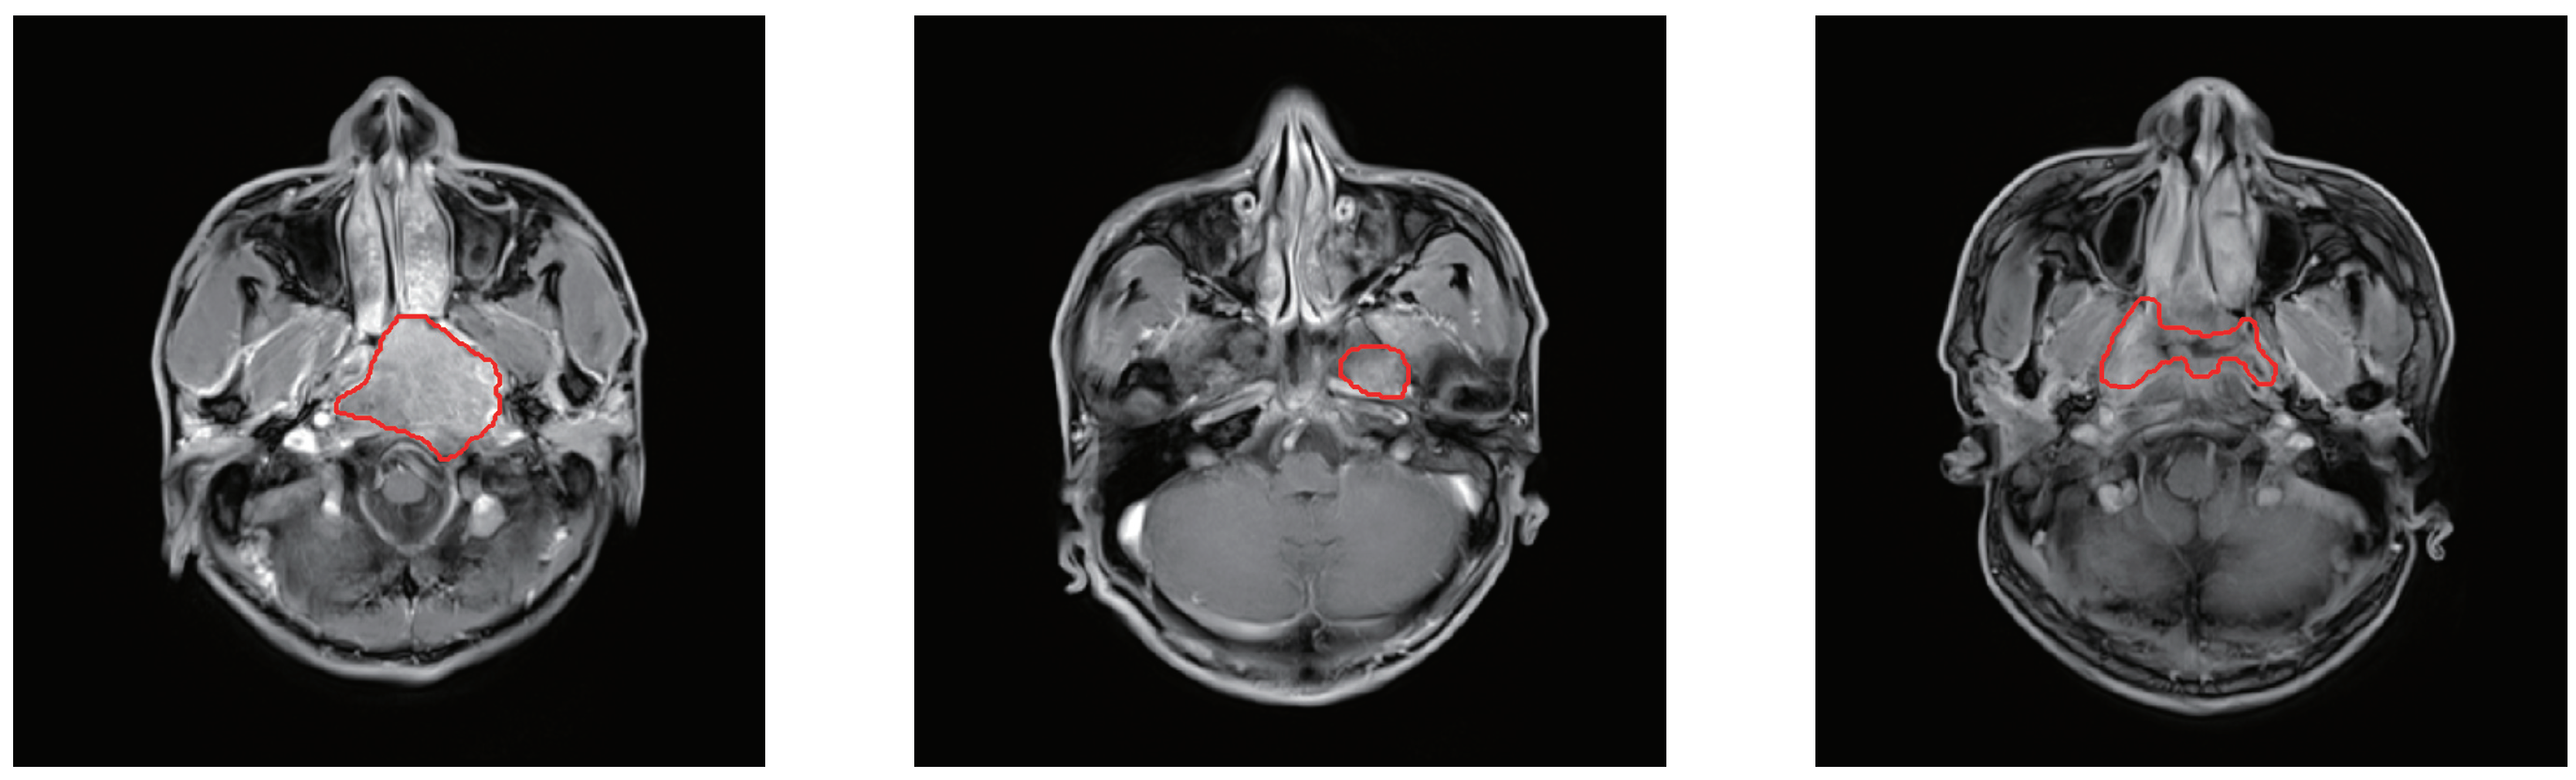

3.1. Dataset Description